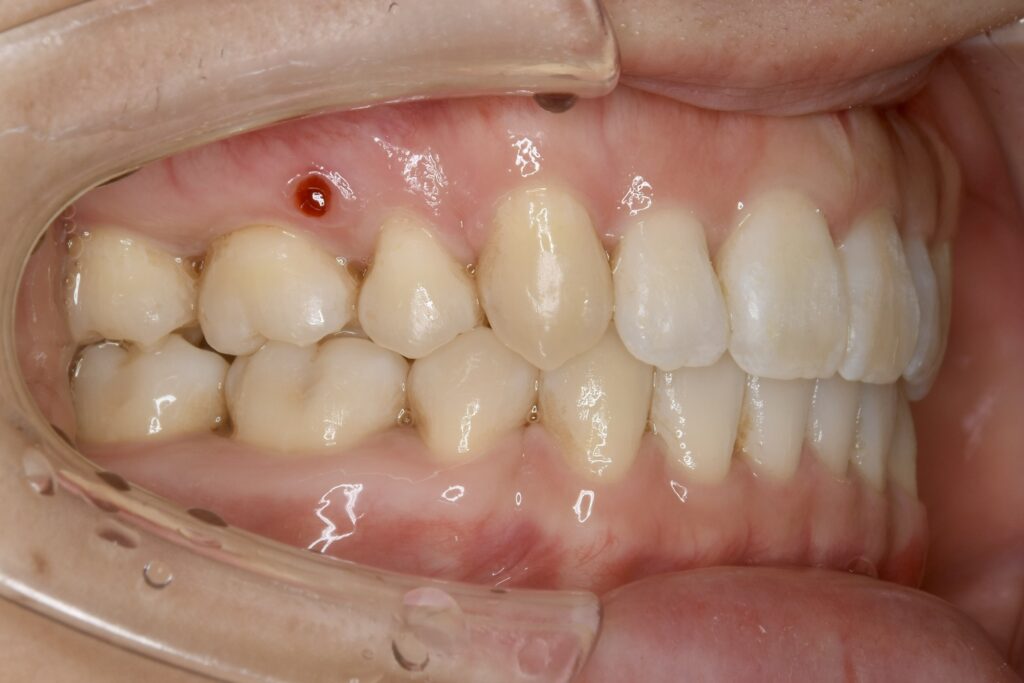

| 主訴 | 上の歯が前に出ている気がして気になる。 |

|---|---|

| 診断名・主な症状 | 叢生 |

| 年齢 | 23歳 |

| 治療内容 | 上の奥歯を後ろに引くことでできたスペースを利用して前歯のデコボコを解消しました。 |

| 使用装置 | 舌側矯正(ワイヤー) 表側矯正(ワイヤー) 矯正用ミニインプラント |

| 抜歯部位 | 抜歯なし |

| 治療期間 | 1年9ヶ月 |

| 通院回数 | 24回 |

| 費用 | 120万円程度(税別) 231 |

| リスク・副作用 | 痛み、歯肉退縮、歯根吸収、抜歯に伴う出血や腫れが生じることがあります。 |